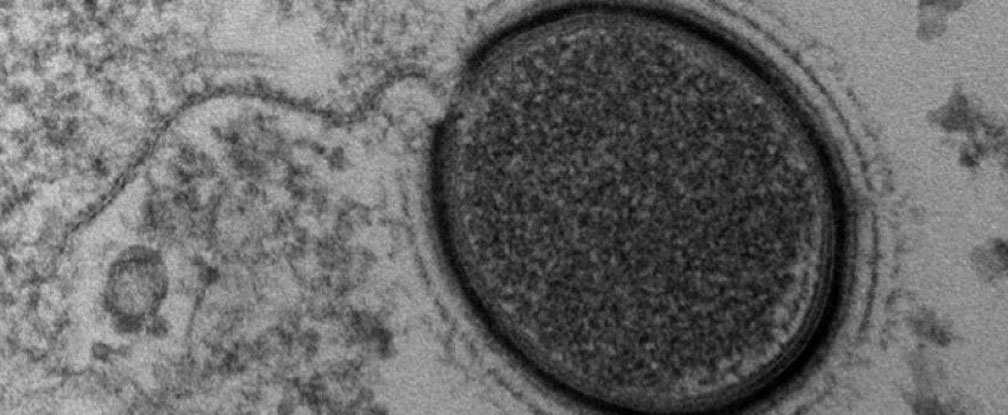

Bilim adamları Sibirya’da bulunan ve 30000 yıldır donmuş olan bir virüsü hayata döndürmeye çalışıyor.

Fransız araştırmacılar 30000 yıldır donmuş halde Sibirya’da yer altında bulunan bir virüsü hayata döndüreceklerini açıkladılar. Mollivirus sibericum, tercümesi “Sibirya’dan yumuşak virüs” olan bu devasa virüs, bu yüzyılda keşfedilen dördüncü böyle virüs. Aynı bilim adamları Pithovirus sibericum’u geçen sene keşfetmişlerdi. Bu tarih öncesi virüsler dev virüsler diye adlandırılıyorlar çünkü bu virüsler mikroskopla görünebiliyorlar. Büyüklükleri yarım mikron’dan